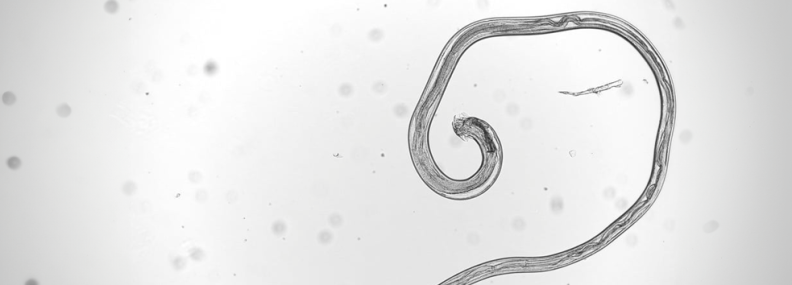

Sheep round worm illustration

Sheep Round Worm

Teladorsagia circumcincta, the brown stomach worm, causes damage to the lining of the abomasum. Grazing lambs may face a sudden high pasture challenge from mid – summer onwards. Heavy infection results in inappetence, diarrhoea, dehydration, weight loss and death.

Trichostrongylus colubriformis and Trichostrongylus vitrinus, the black scour worms, live in the small intestine and typically produce disease later in the year among store lambs and ewe lamb replacements. Mixed infections with other species are common, with worm damage causing dark, watery diarrhoea, weight loss, dehydration, loss of appetite and potentially death.

Haemonchus contortus, the barber’s pole worm, inhabits the abomasum. The juvenile and adult stages are blood feeders, which results in tissue damage and blood loss. Both adult sheep and lambs can be affected by haemonchosis with cases often seen in the mid to late summer period. Where worm numbers are low, infection may manifest as illthrift, anaemia and submandibular oedema - ‘bottle jaw’, but it does not cause diarrhoea. In sheep with a heavier worm.

Gastrointestinal nematode species including Teladorsagia circumcincta, Trichostrongylus colubriformis, Trichostrongylus vitrinus,and Haemonchus contortus, have a direct lifecycle. Female adult worms lays eggs within the sheep, these eggs are shed in the faeces onto the pasture where they mature into an infective stage that is ingested by the sheep.